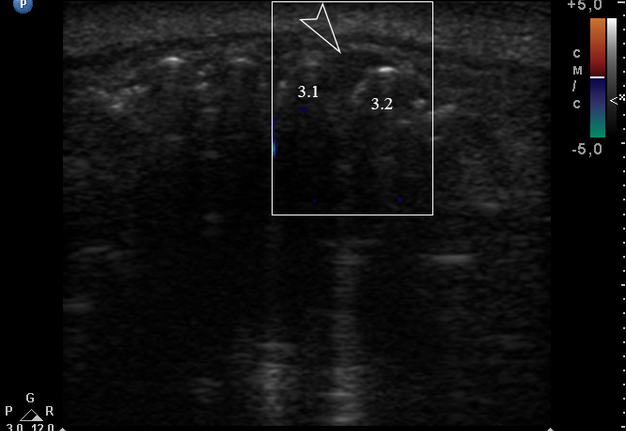

An extraoral ultrasound examination was performed by O.S.C., an expert physician (>18 years of experience in head and neck USG), on the day of admission in the department. A HD11 XE USG system (2007, the Philips, Amsterdam, the Netherlands) equipped with a linear L12-3 transducer (frequency fange: 3.0-12.0 MHz; aperture: 38 mm) was used for the examination, fixing a 3-cm of ultrasonography (penetration) depth.

Anterior part of the neoplasm at the vestibular aspect of the lower teeth measured 0.34 x 0.38 cm (Fig 3). Upon the gray-scale USG the anterior part portion of the neoplasm vizualized as homogenous hypoechoic lesion with no signs of calcifications. Color Doppler USG showed no vascularity within the vestibular portion of the neoplasm (Fig 4).